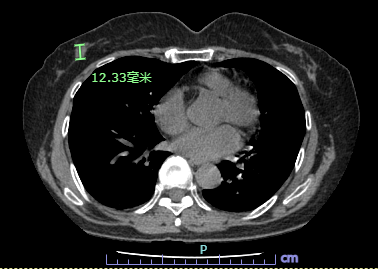

2021-7-14胸部CT:右侧乳腺区见大小约1.4cmX0.8cmX1.9cm结节影。

??图1.胸部CT